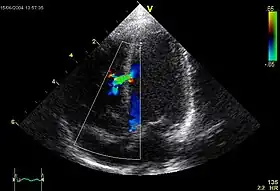

![]() An abnormal echocardiogram: Image shows a midmuscular ventricular septal defect. The trace in the lower left shows the cardiac cycle and the red mark the time in the cardiac cycle when the image was captured. Colors are used to represent the velocity and direction of blood flow. | |

Echocardiography can help detect cardiomyopathies, such as hypertrophic cardiomyopathy, and dilated cardiomyopathy. The use of stress echocardiography may also help determine whether any chest pain or associated symptoms are related to heart disease. The biggest advantage of echocardiography is that it is not invasive (does not involve breaking the skin or entering body cavities) and has no known risks or side effects.[4] Not only can an echocardiogram create ultrasound images of heart structures, but it can also produce accurate assessment of the blood flowing through the heart by Doppler echocardiography, using pulsed- or continuous-wave Doppler ultrasound. This allows assessment of both normal and abnormal blood flow through the heart. Color Doppler, as well as spectral Doppler, is used to visualize any abnormal communications between the left and right sides of the heart, any leaking of blood through the valves (valvular regurgitation), and estimate how well the valves open (or do not open in the case of valvular stenosis). The Doppler technique can also be used for tissue motion and velocity measurement, by tissue Doppler echocardiography.